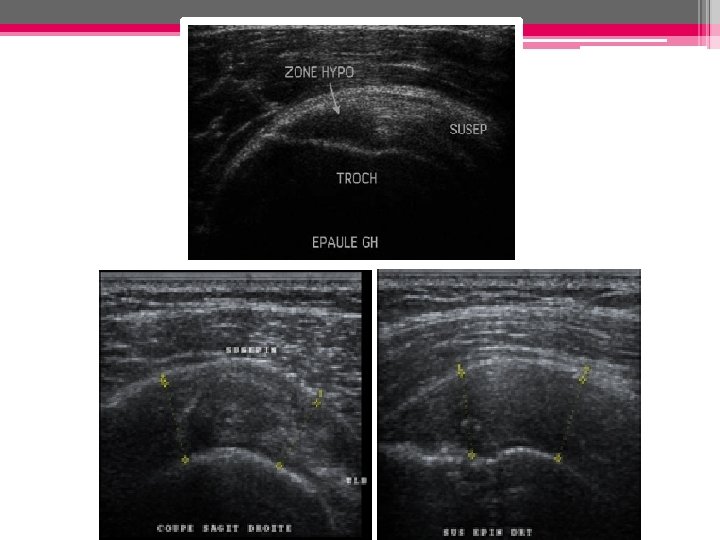

ECHOGRAPHIE: • Rupture transfixiante signes directs: - Méplat tendineux ou marche d’escalier - Défect tendineux focal (hypo ou anéchogène (hyper très rare) - Amincissement du tendon - Disparition du tendon

Rupture transfixiante Défect tendineux focal anéchogène du sus-épineux Amincissement du tendon sus-épineux Absence d’individualisation du tendon ; le muscle deltoide vient directement au contact de la tete humérale

• Rupture partielle (non transfixiante): - Zone hypoéchogène ++ hyperéchogène entourée d’une zone hypo hyper - Face articulaire (profonde)/bursale (superficielle)/ intra-tendineuse

◊ Ruptures partielles profondes

◊ Ruptures partielles superficielles:

• Rupture complète: Rupture totale: important amincissement et perte de la convexité supérieure du tendon Rupture totale: désinsertion des fibres distales remplacées par du liquide )

Supraspinatus tendon, longitudinal view. Massive supraspinatus tendon tear with tendon nonvisualization and joint fluid collection. The stump of the supraspinatus tendon (arrows) is retracted.